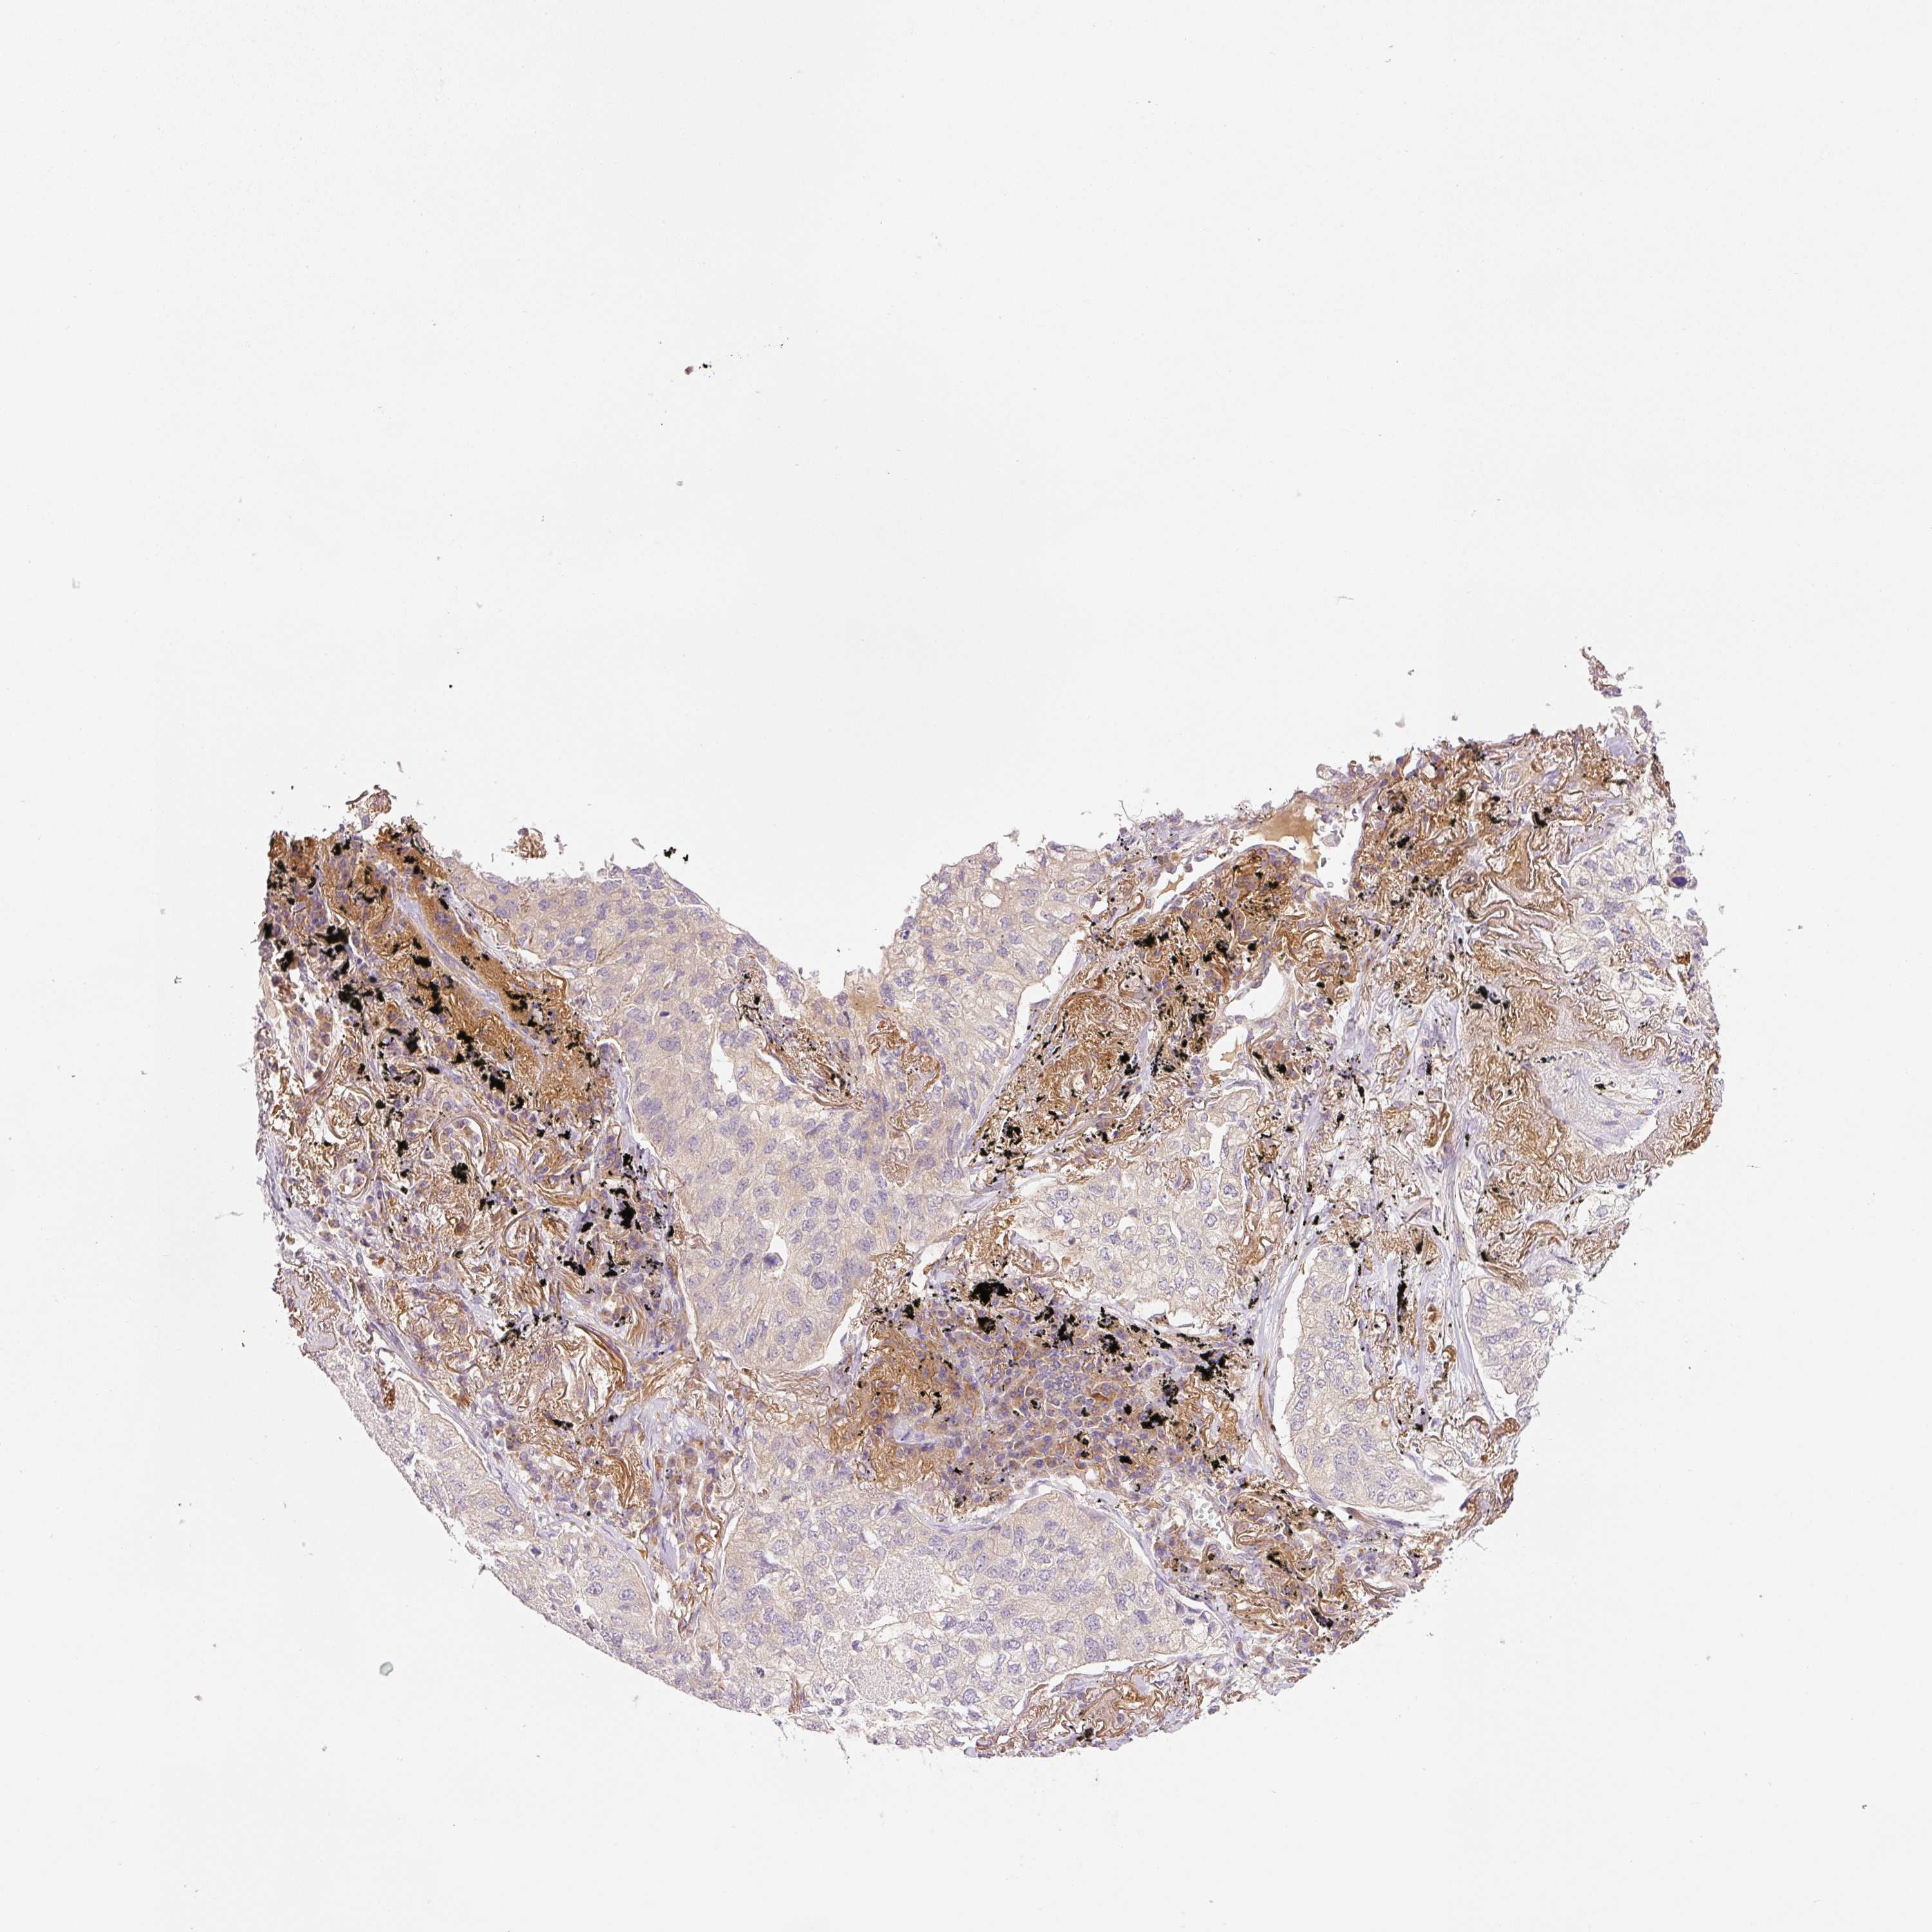

CANCER LUNG CANCER Show tissue menu

LUAD TCGA LUAD VALIDATION LUSC TCGA LUSC VALIDATION PROTEIN LUAD CPTAC PROTEIN LUSC CPTAC PROTEIN EXPRESSION